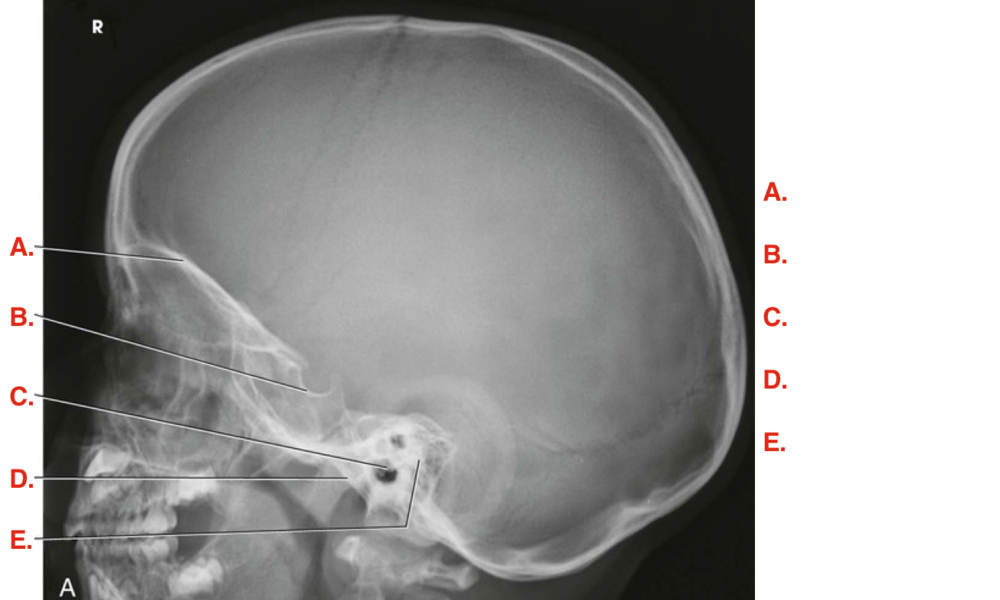

Question 2

Question

Label the image

Image:

8b9afdb2-f0fc-4b7e-953e-ae39baf02278 (image/png)

Answer

supraorbital margin

sella turcica

external acoustic meatus

temporomandibular joint

petrous portion